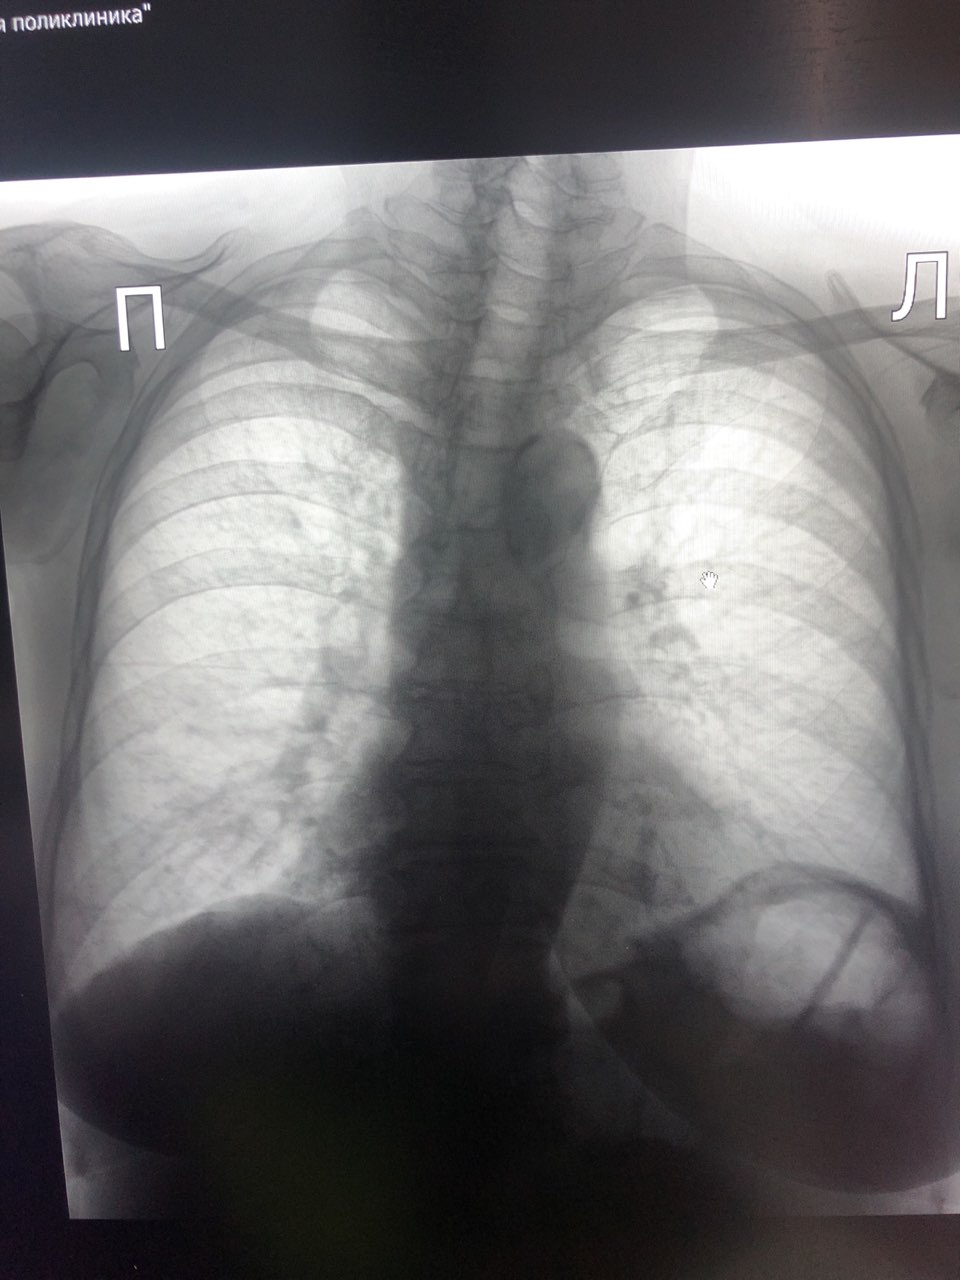

Добрый день , коллеги . Посмотрите снимок пожалуйста . Женщина 1941 г. , неделю температура и кашель . Экспресс тест на ковид отрицательный

65 лет, пациент из кардиологии, возрастные изменения, застой в МКК, аортосклероз?